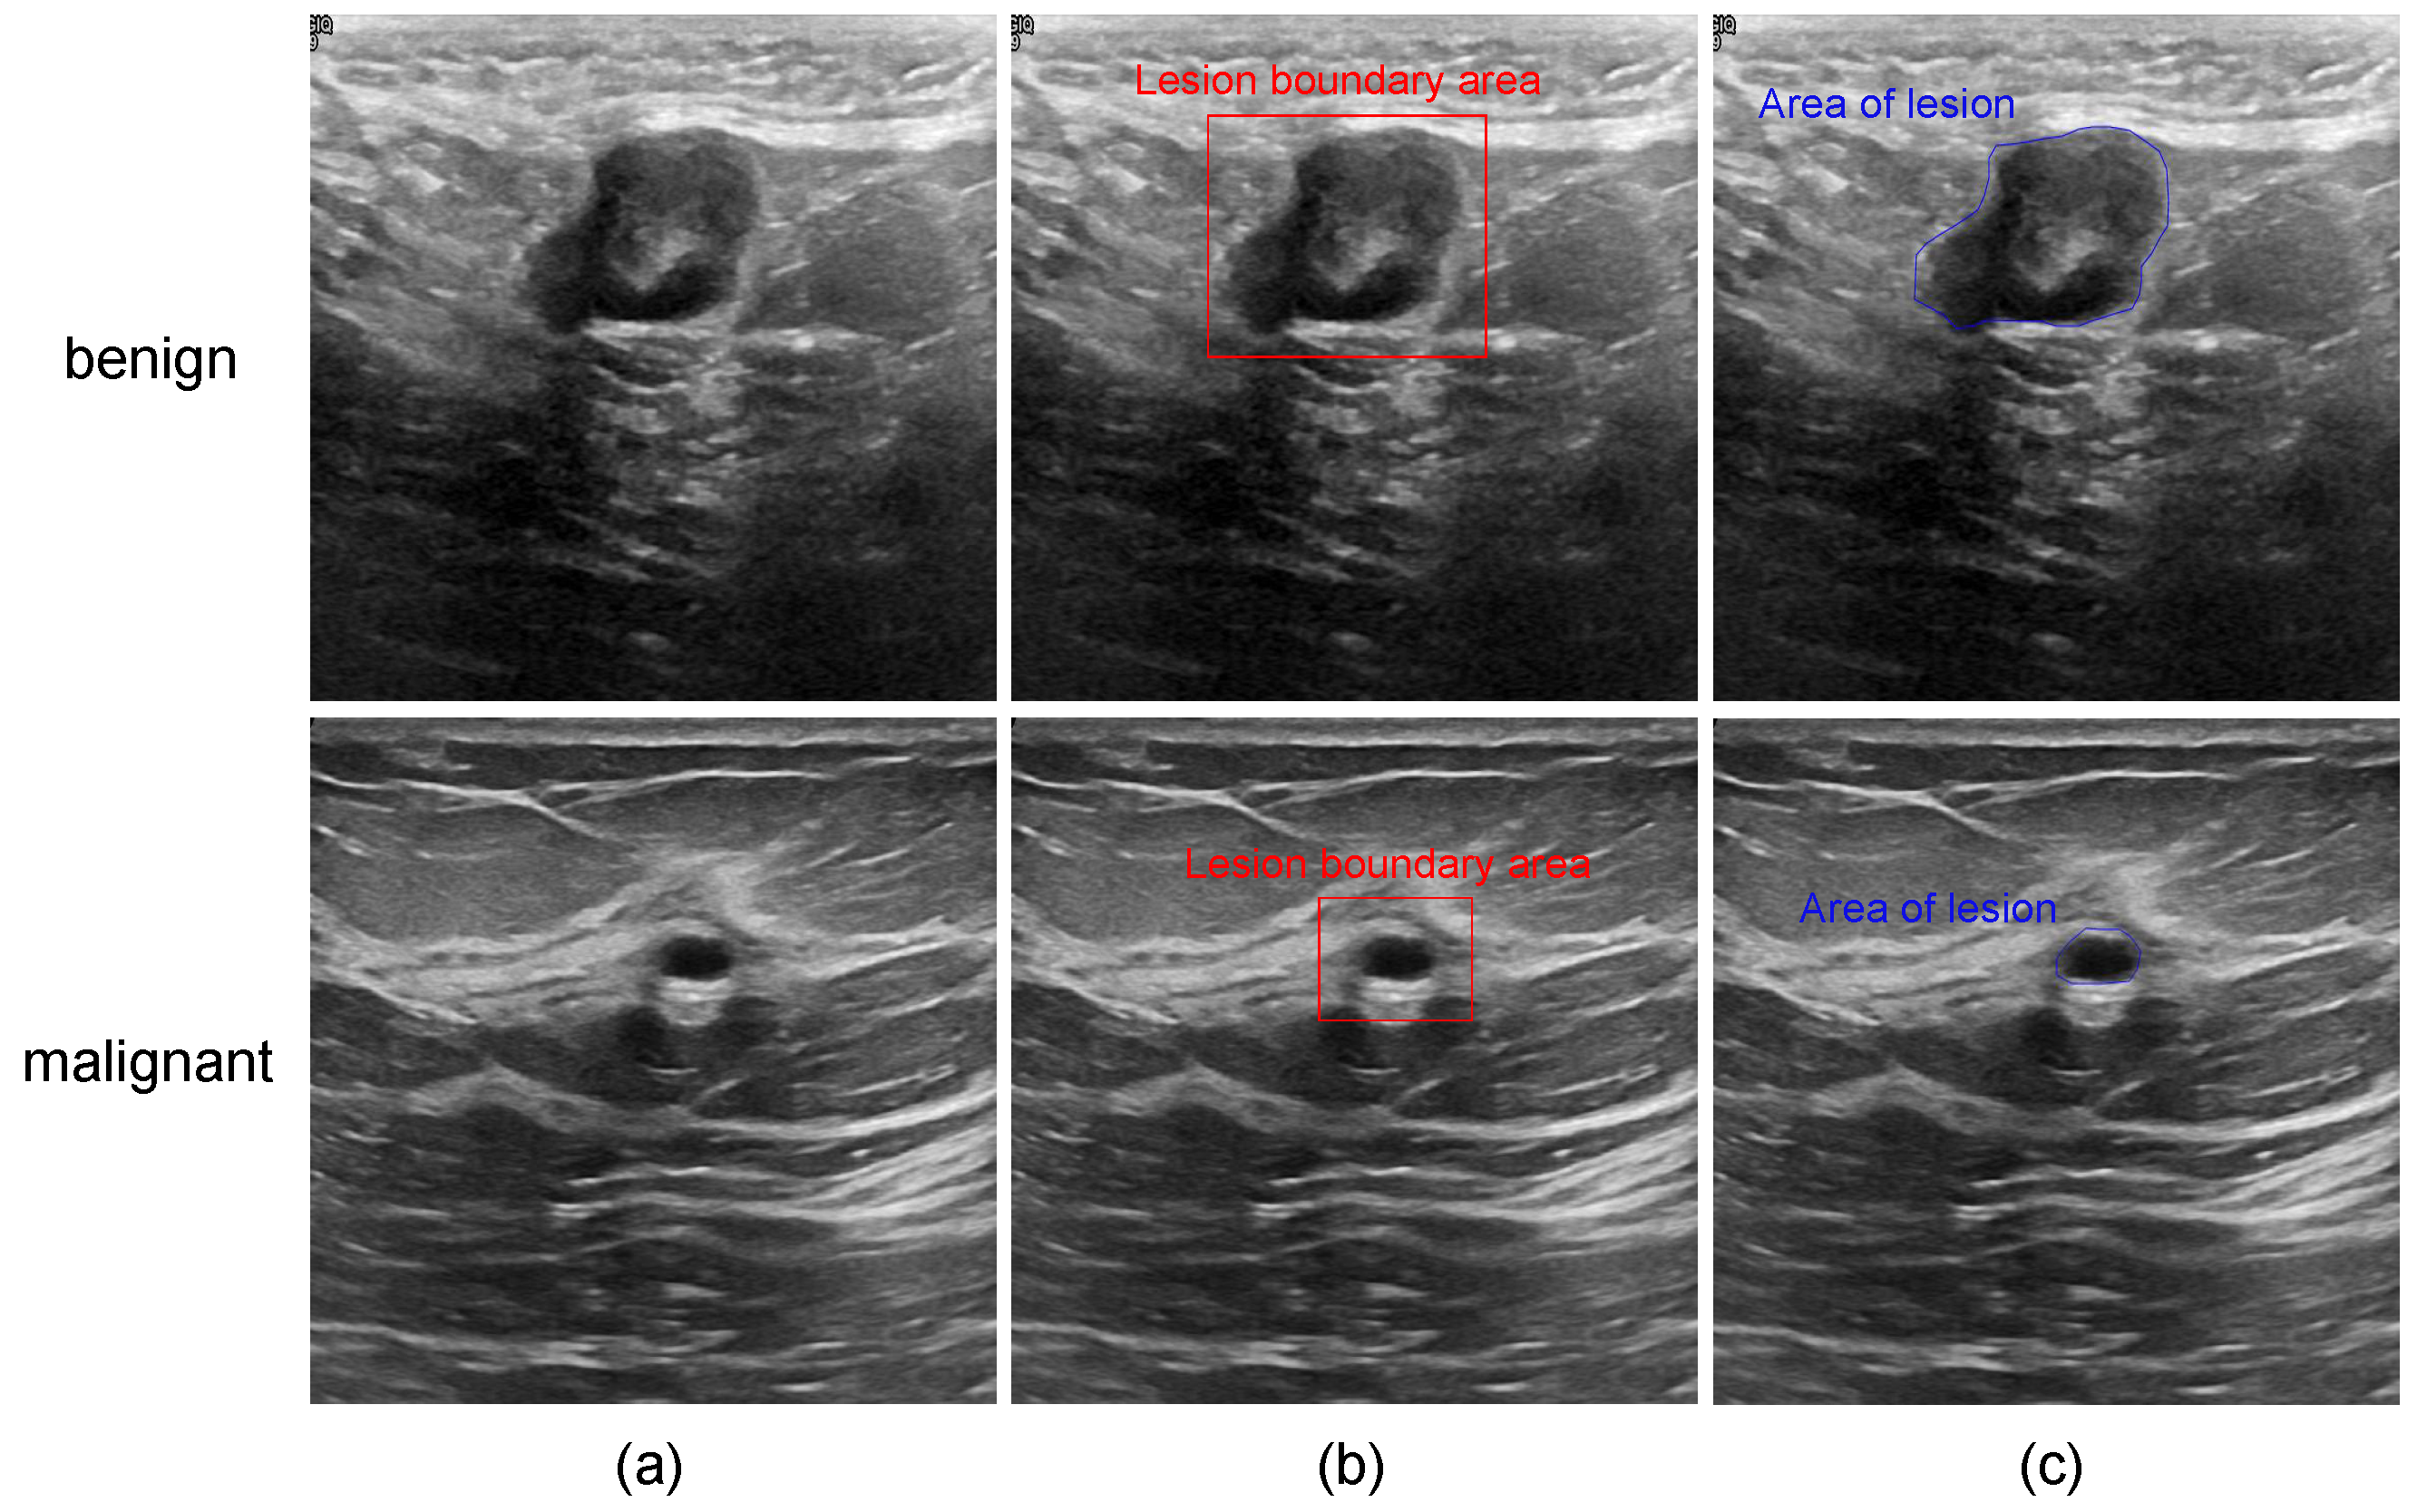

- Insufficient segmentation performance: Breast ultrasound images pose challenges such as speckle noise, blurry boundaries, and low contrast, making tumor segmentation more challenging.

4.1. Experiment Materials